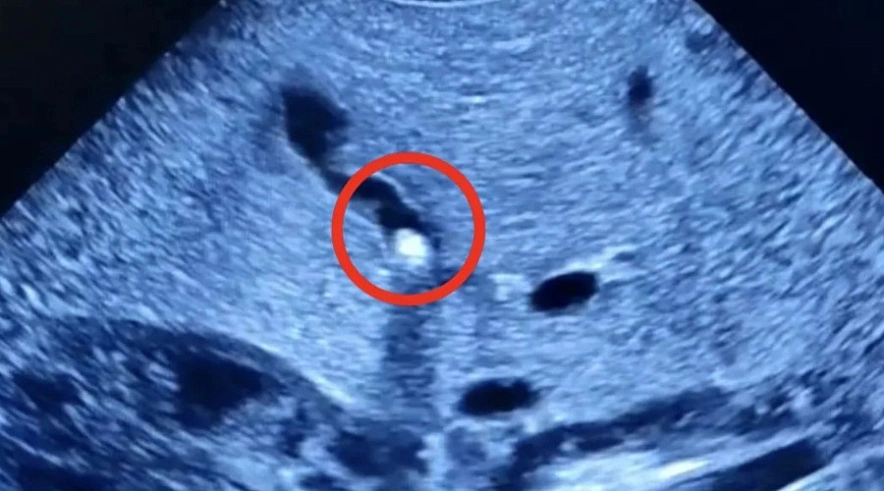

Как сообщает Балаковская городская клиническая больница (БГКБ), к медикам обратилась мама 1,5-месячного малыша. Она пожаловалась на плохую прибавку массы тела, желтушное окрашивание кожи и склер у своего ребенка. После обследования выяснилось, что желчный проток частично закрыт камнем небольших размеров.